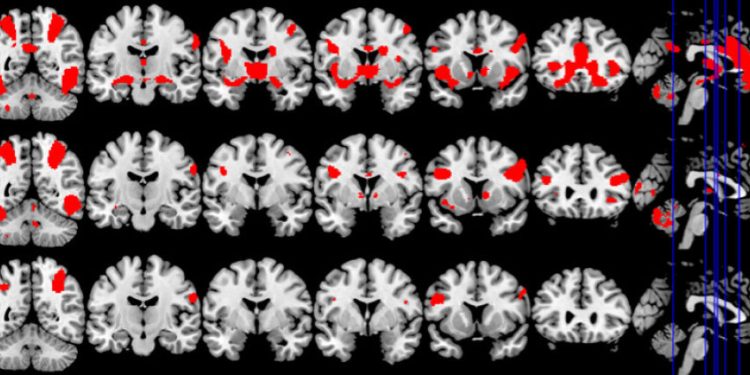

وقد عرض على المشاركين في الدراسة سلسلة من أشرطة الفيديو القصيرة التي تحتوي على محتوى جنسي صريح أو رياضة، في حين تم رصد نشاط الدماغ باستخدام التصوير بالرنين المغناطيسي الوظيفي (fMRI)، والذي يَستخدم إشارة تعتمد على مستوى الأوكسجين في الدم (BOLD) لقياس نشاط المخ.

وجد الباحثون أن ثلاث مناطق على وجه الخصوص كانت أكثر نشاطًا في أدمغة المرضى مع وجود سلوك جنسي قهري مقارنة مع المتطوعين الأصحاء، بشكل ملحوظ، كانت هذه المناطق هي كالآتي: (المخطط البطني “Ventral Striatum”، الأمامية الظهرية الحزامية “Dorsal Anterior Cingulate” واللوزة “Amygdala”)، وهي نفس المناطق النشطة بشكل خاص أيضًا لدى مدمني المخدرات عند ظهور المحفزات كالمخدرات، وتتشارك في منطقة المُخطط البطني (Ventral Striatum) أثناء معالجة المكافأة والدافع، في حين أن المنطقة الأمامية الظهرية الحزامية (Dorsal Anterior Cingulate) متورطة في توقع المكافآت وشغف المخدرات، وتشارك اللوزة (Amygdala) في معالجة الأحداث والانفعالات العاطفية المهمة.

وكما كان متوقعًا، أظهر المرضى الذين يعانون من سلوك جنسي قهري (Compulsive Sexual Behaviour) مستويات أعلى من الرغبة بعد مشاهدة أشرطة الفيديو الجنسية الصريحة، وارتبطت الرغبة أيضًا بارتفاع التفاعلات بين المناطق الدماغية المذكورة سابقًا ،لكن كان التفاعل بينها محدودًا بالمقارنة مع أشرطة الفيديو الرياضية الإيحائية.